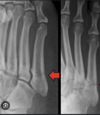

Fx de Jones Base del 5to metacarpiano